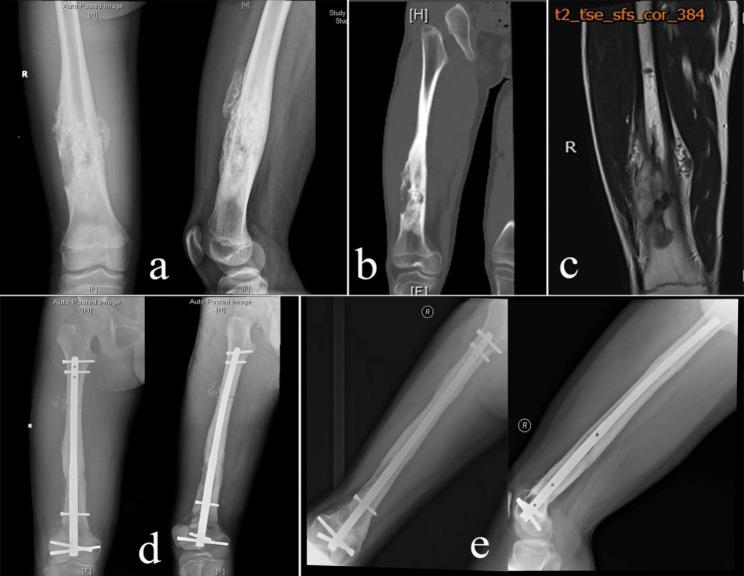

For patients with malignant limb tumors, salvage surgery can be achieved using endoprosthesis or biological reconstructions like allograft or autograft. In carefully selected patients, resected bone can be recycled after sterilization using methods like autoclaving, irradiation, pasteurization or freezing with liquid nitrogen. We evaluated the clinical outcome and complications of malignant limb tumors treated with intercalary resection and frozen autograft reconstruction.

We reviewed 33 patients whose malignant bone tumors were treated by wide resection and reconstruction with recycling liquid nitrogen-treated autografts between 2006 and 2017. Limb function, bone union at the osteotomy site and complications were evaluated. Functional outcome was assessed using the Musculoskeletal Tumor Society (MSTS) scoring system.

The cohort comprised 16 males and 17 females, with a mean age of 35.4 years (14-76 years). The most common tumor was osteosarcoma (7 cases). Tumors were located in the humerus (5), ulna (1), femur (10) and tibia (17). The mean follow-up was 49.9 months (range 12-127 months). Of the 33 patients, 16 remained disease-free, and 3 were alive with disease. The mean size of the defect after tumor resection was 11.6 cm (range 6-25 cm). Bone union was achieved in 32 patients, with a mean union time of 8.8 months (range 4-18 months). Complications included 1 graft nonunion, 2 infections (1 superficial, 1 deep infection), 1 leg length discrepancy, 2 graft fractures and 3 local recurrences. The mean MSTS score was 87.2% (range 70-100%).

Liquid nitrogen-treated tumor-bearing autograft is an effective option for biological reconstruction after meta-/diaphyseal tumor resection of long bones. This method has excellent clinical outcomes and is especially recommended for patients with no severe osteolytic bone tumors.